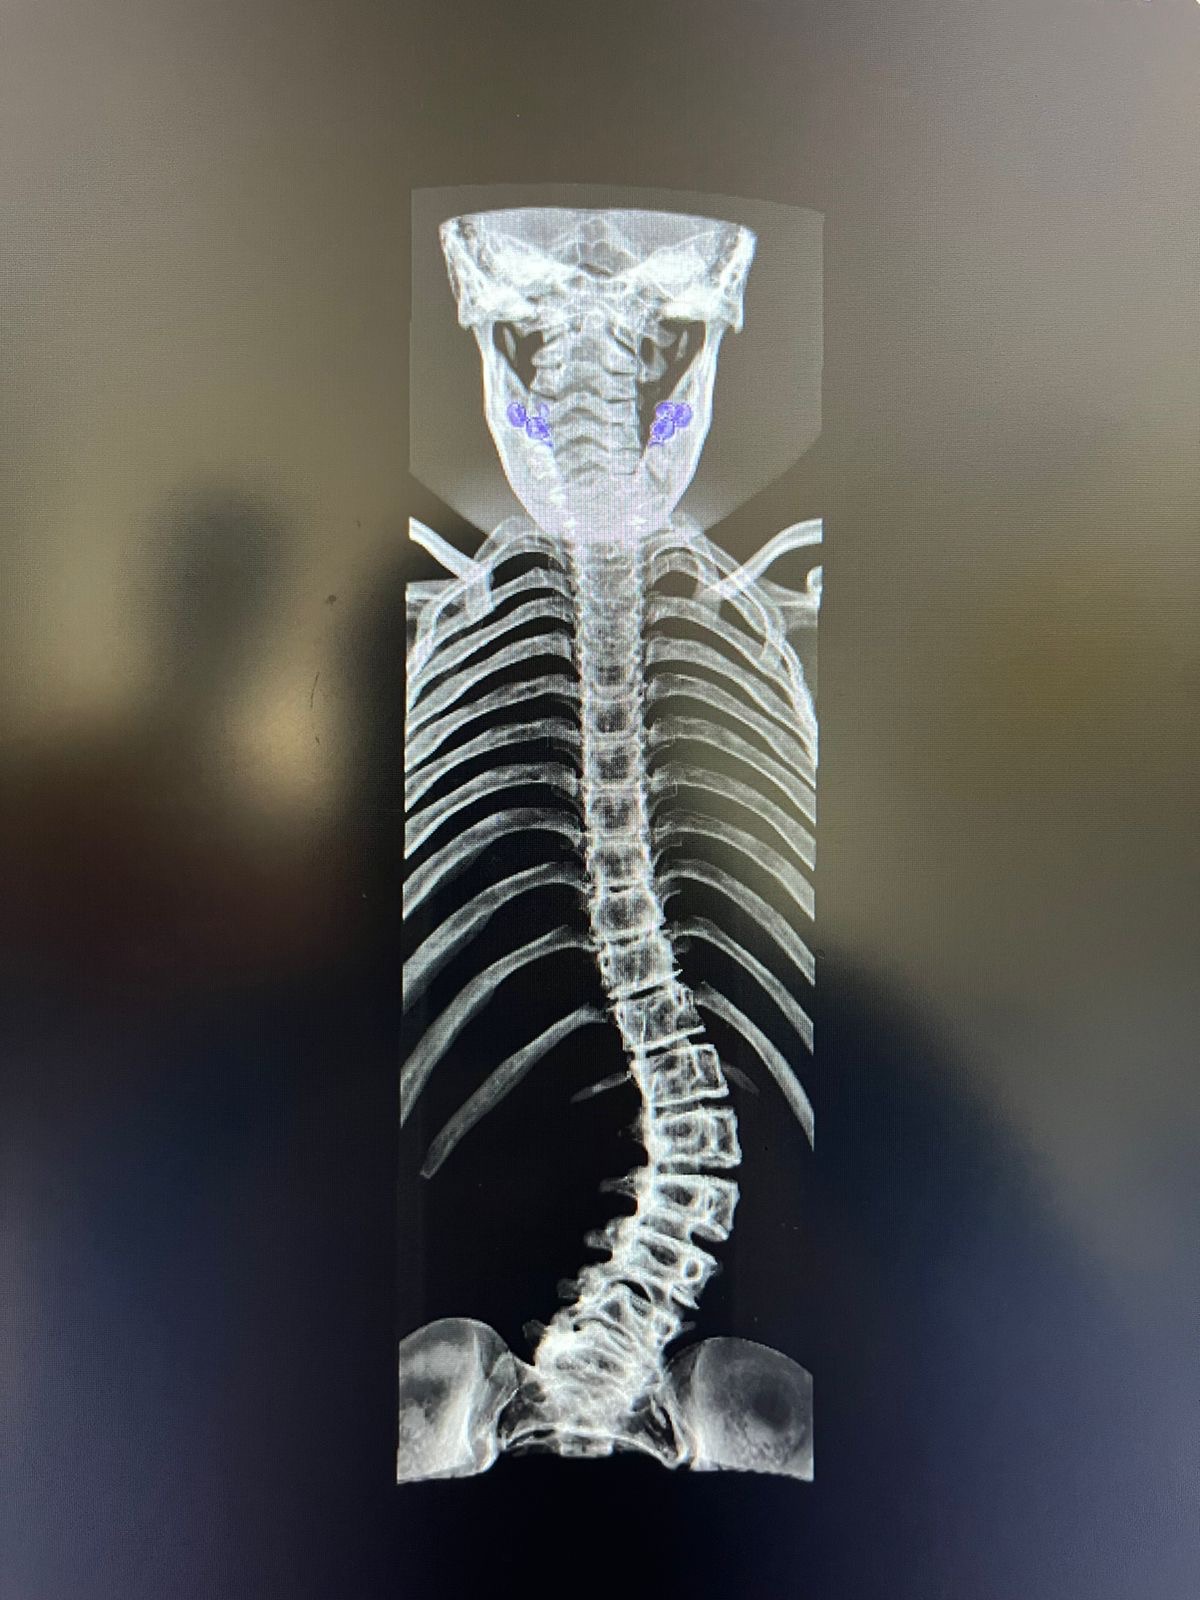

Hi everyone! We’re fundraising for my cousin in Colombia. His name is Tomas Garcia, he is 13 years old, and due to a rare disease called Ehlers-Danlos syndrome, he has a significant deviation in his spine, which requires one or more surgeries to prevent it from increasing further and hindering the normal growth of his lung and kidney. These surgeries will also allow him to lead a normal life. For this reason, we are asking for any kind of support. as it is a bit difficult for his father to cover all the expenses required before, during, and after the surgery. We are from a coffee-growing city in Colombia called Armenia.